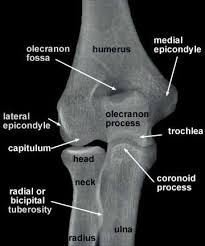

The common extensor tendon attaches to the lateral epicondyle, acting as the common attachment for the superficial extensor muscles of the forearm. The lateral epicondyle of the humerus is a large, tuberculated eminence, curved a little forward, and giving attachment to the radial collateral ligament of the elbow joint, and to a tendon common to the origin of the supinator and some of the extensor muscles. Tennis elbow assessment explore the. Related online courses on physioplus. Lateral epicondylitis is defined as a pathologic condition of the wrist extensor muscles at their origin on the lateral humeral epicondyle. This area can become tender to the touch. Pain is felt over the lateral epicondyle and radiates down forearm. Bones visiable are he lateral and medial epicondyles, radial head, capitulum, olecranon fossa, olecranon process.

An ununited fracture of the lateral condyle can lead to. The medial and lateral epicondyles are small bony tuberosities on the distal end of the humerus (fig. Lateral elbow is in contact with ir. Tennis elbow assessment online course: Resisted wrist extension with elbow fully extended.

Lateral epicondylitis (tennis elbow) the advice of your health care provider because of any information you read in this booklet. Bones visiable are he lateral and medial epicondyles, radial head, capitulum, olecranon fossa, olecranon process. Pain upon resisted wrist extension. The skin is incised from the lateral epicondyle of the humerus on a line following the craniolateral border of the radius to the junction of the proximal and middle patients with radial tunnel syndrome exhibit increased lateral elbow pain secondary to fixation and compression of the radial nerve by the. Resisted wrist extension with elbow fully extended.